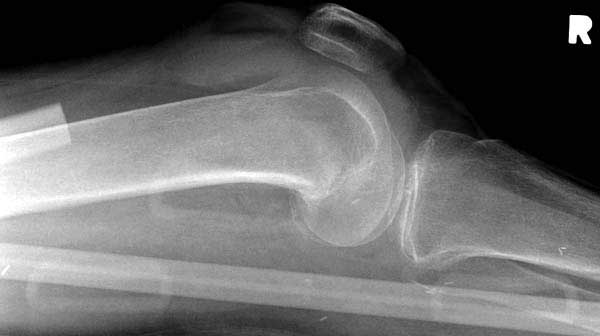

Обычно после чрезвертельных переломов, за исключением молодых, у пожилых остается нестабильность при движении. Часто падают и после 3х мес. в результате падения обнаружен перипротезный перелом (22-23), который зафиксирован Синтез пластиной.

Имя     : 22 distal fem fx.jpg

Тип     : image/jpg

Размер  : 49238 байтов

Описание: отсутствует

Url     : http://weborto.net:8080/pipermail/ortho/attachments/20120510/52aada75/attachment-0044.jpg

----------- следущая часть -----------

Вложение не в текстовом формате было извлечено…

Имя     : 23 distal fem fx.lat.jpg

Размер  : 26162 байтов

Url     : http://weborto.net:8080/pipermail/ortho/attachments/20120510/52aada75/attachment-0045.jpg